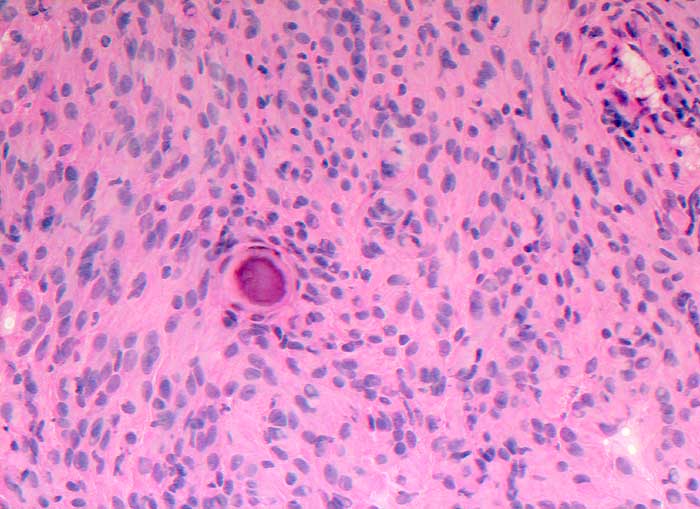

Im Schnellschnitt sind psammomatöse Verkalkungen und meningotheliale Zellen ohne Atypien erkennbar.

Zytologische Diagnose: Meningeom. Am ehesten handelt es sich um einen transitionalen Typ mit häufigem Nachweis von Wirbelbildungen und Psammomkörperchen.

Schnellschnitt

200